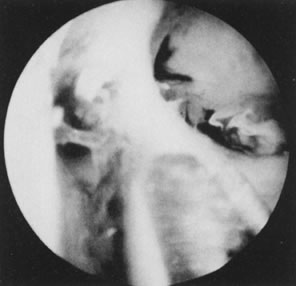

Fig. 30. ( A) and ( B )Resectoscopic division of broad uterine septum with knife electrode.

The resectoscope may also be used to transect the septum, adding the advantage of coagulation-transection, which is most beneficial when dealing with very broad septa. A special straight knife or a loop oriented forward can be used for this purpose, using the blended current for simultaneous cutting and coagulation. Care should be taken not to overcorrect the defect, because bleeding may not be a warning sign of invading myometrium when blended current (cutting/coagulating) is used. Only fluids without electrolytes should be used, and laparoscopic monitoring is most helpful (Fig. 30).26